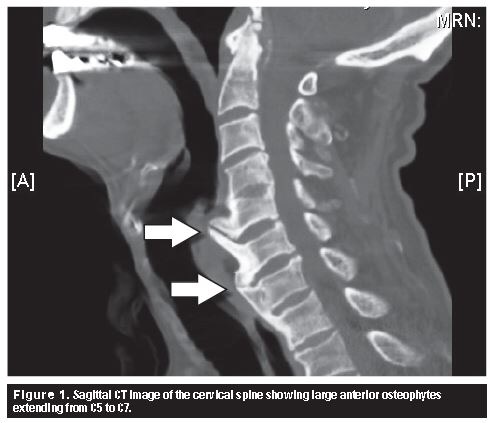

This can result in anterior vertebral osteophytosis (bone spurs) and discs that bulge anteriorly. These are attempts to create more surface area on the anterior surface, when clearly the neck biomechanics need to be improved.

Bone spurring is a particular concern for those with long-standing cervical stability loss in flexion, since the spurs create difficulty in swallowing.